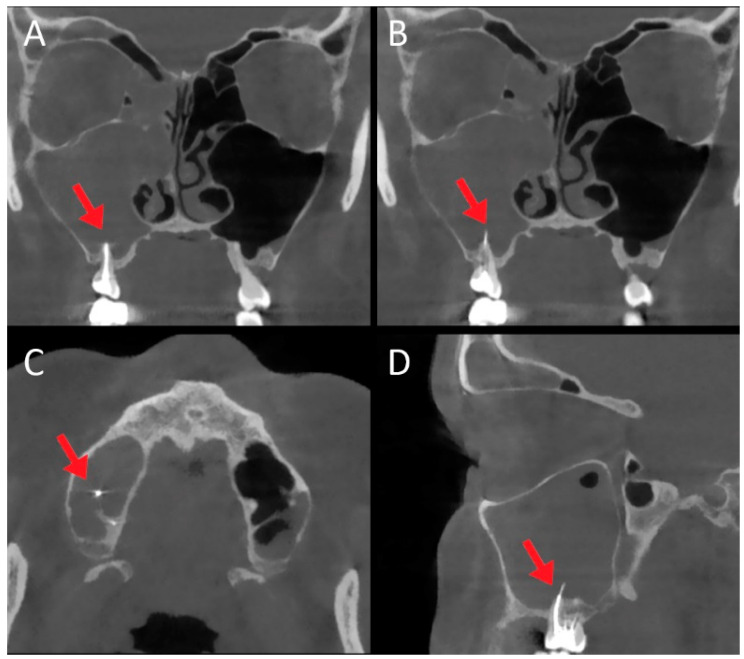

Female patient, 52 years old, complaining of facial pain, nasal obstruction, and rhinorrhea with a history of endodontic treatment 5 months earlier. CT ((A,B): coronal scan; (C): axial scan; (D): sagittal scan) revealed chronic right maxillary sinusitis extending to the right frontal sinus, and the presence of endodontic material in the right maxillary sinus (red arrows). Endoscopic surgery was performed before subsequent revision of dental surgery.